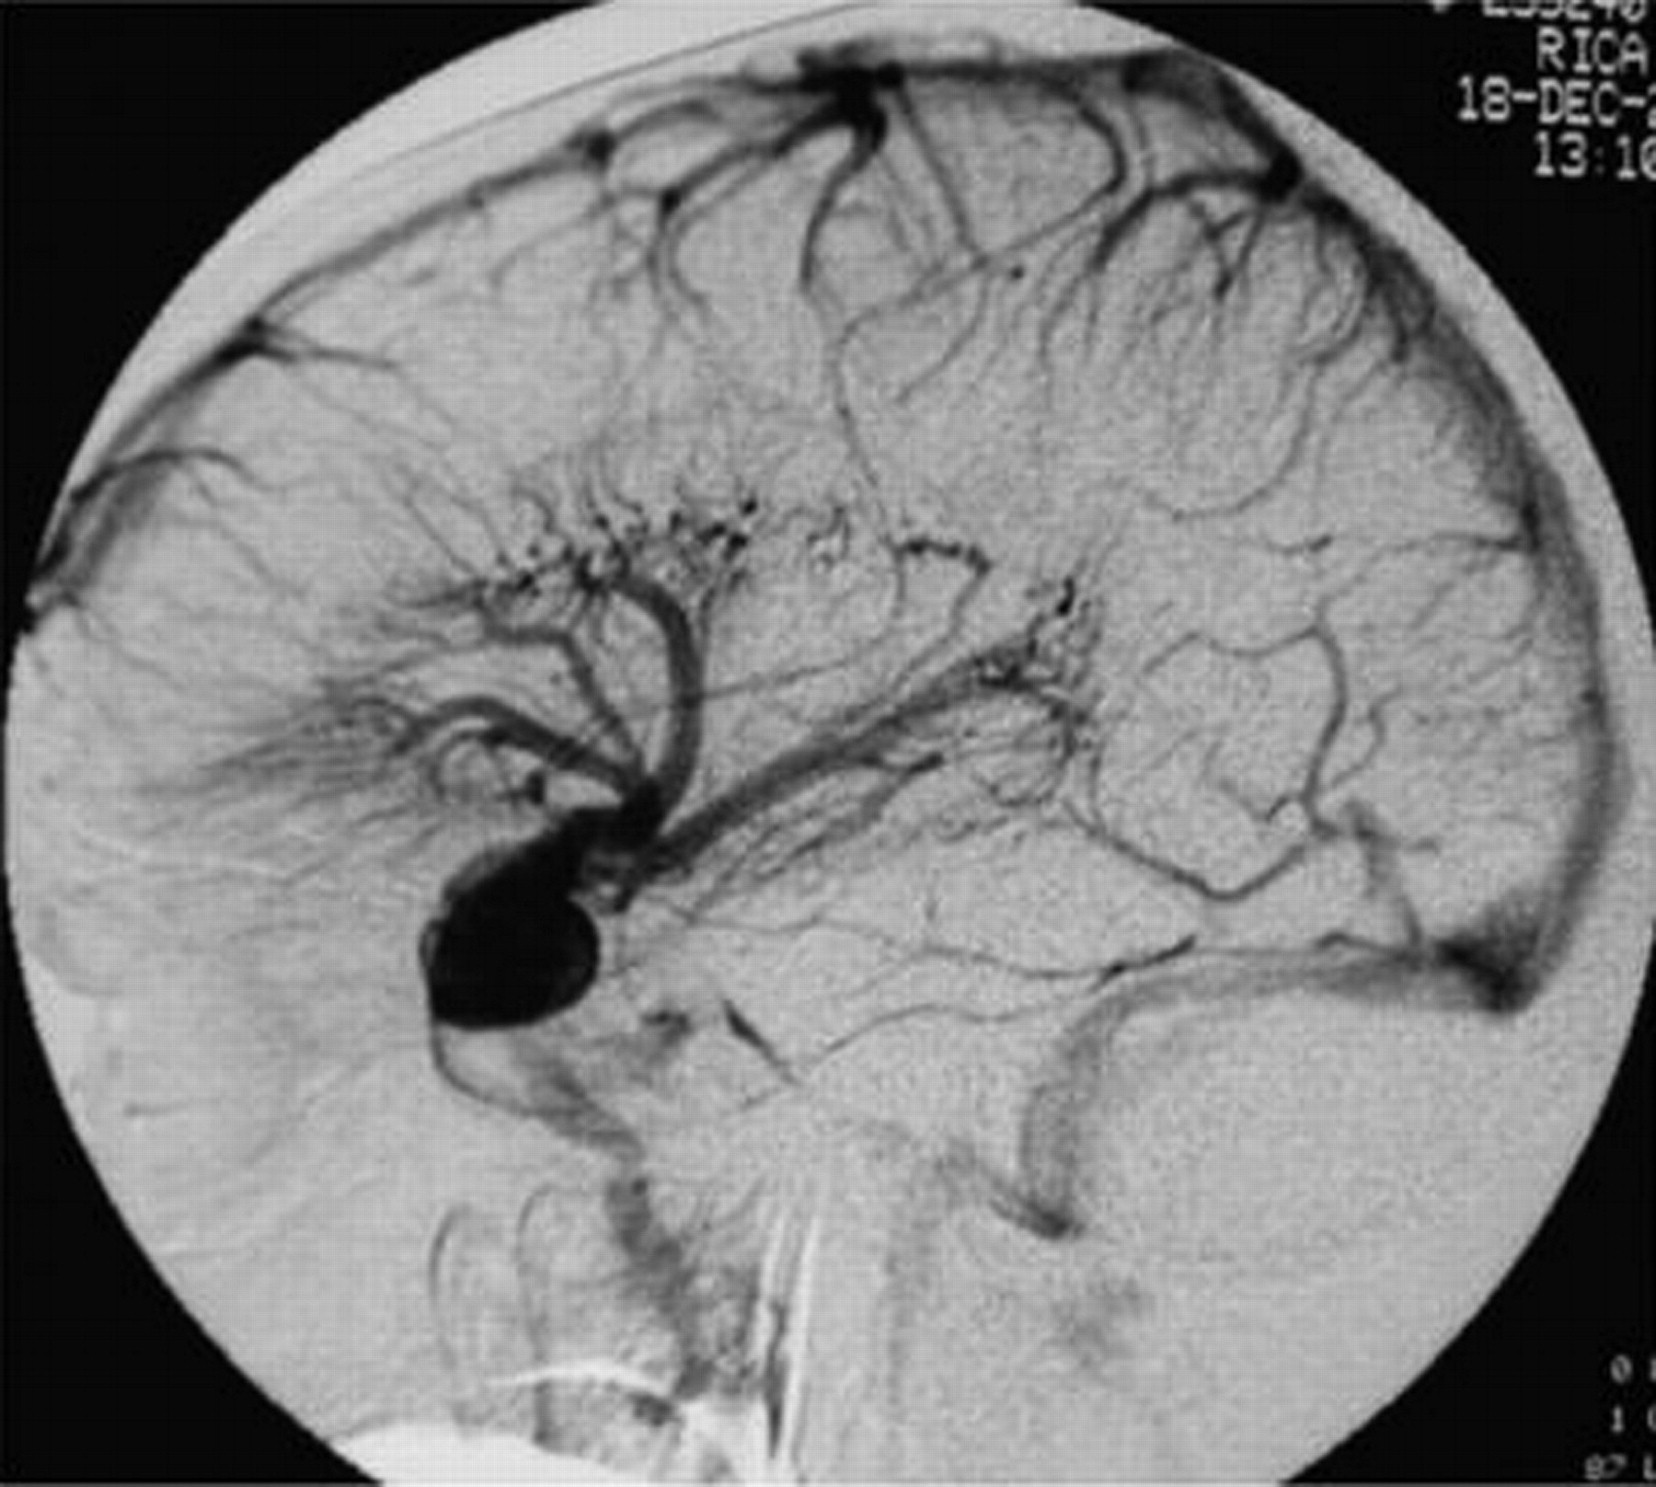

Мр картина венозной ангиомы левой гемисферы мозжечка - 96 фото